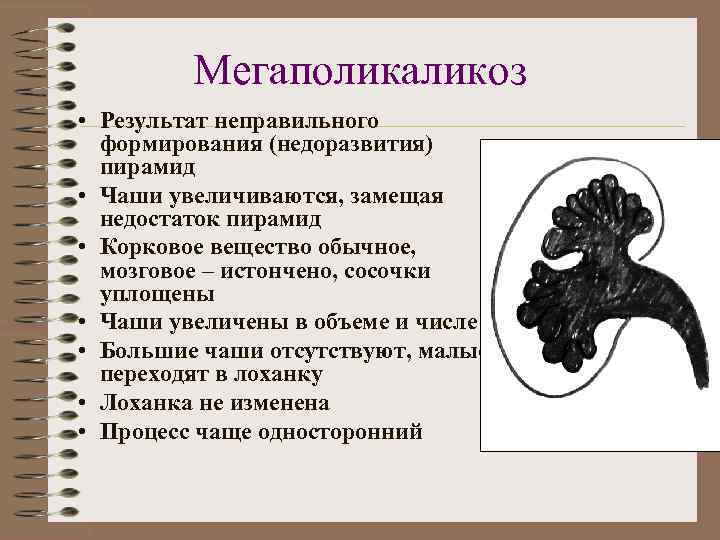

Мегаполикаликоз • Результат неправильного формирования (недоразвития) пирамид • Чаши увеличиваются, замещая недостаток пирамид • Корковое вещество обычное, мозговое – истончено, сосочки уплощены • Чаши увеличены в объеме и числе • Большие чаши отсутствуют, малые переходят в лоханку • Лоханка не изменена • Процесс чаще односторонний

Мегаполикаликоз • Количество малых чаш превышает 12 • Чаши расширены, имеют фасеточную форму, расположены в толще паренхимы • Выделительная функция замедлена • Лоханка не изменена